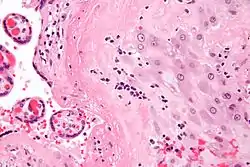

Micrograph of a chronic deciduitis, showing the characteristic plasma cells. H&E stain. |

Chronic deciduitis is a type of long-lasting inflammation that arises in pregnancy and affects the endometrial stromal tissue (decidua).

It is associated with preterm labour.[1] The diagnosis rests primarily on the presence of plasma cells.[2]